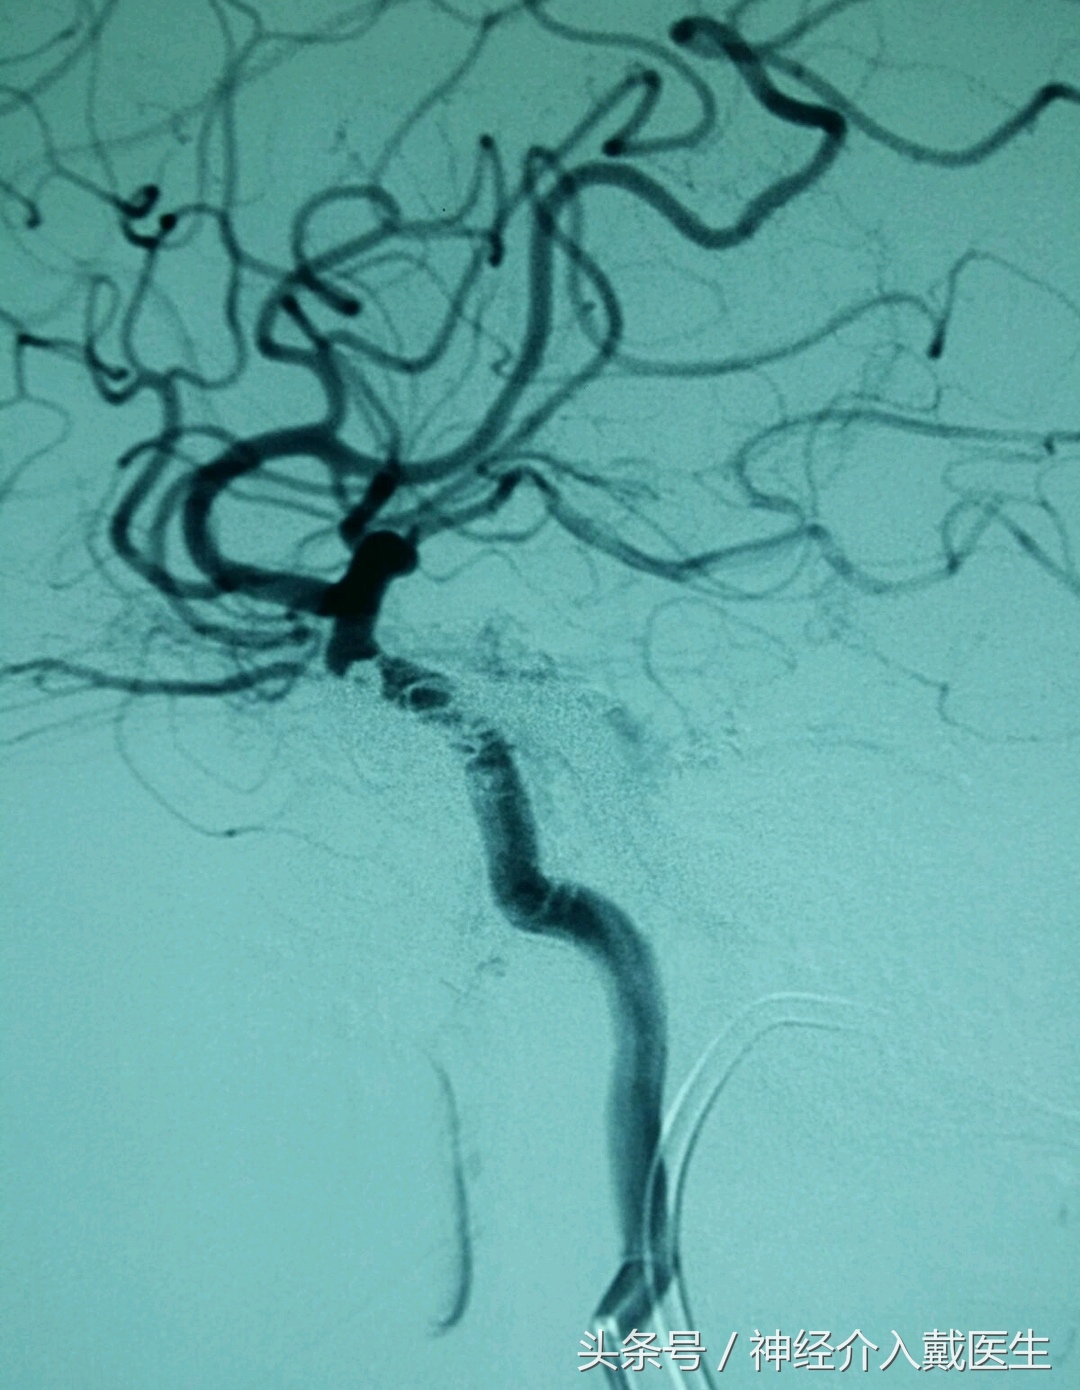

手术后效果侧位像

介入手术顺利完成,瘘口完全封闭,脑血流恢复正常,颅内杂音立即消失,眼结膜充血逐步消失。